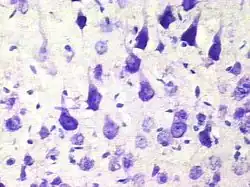

Пирамидальный нейрон

Пирамидальные нейроны, или пирамидные нейроны — основные возбудительные нейроны мозга млекопитающих. Также обнаруживаются у рыб, птиц, рептилий. Напоминают по форме пирамиду, из которой вверх ведёт большой апикальный дендрит; имеют один аксон, идущий вниз, и множество базальных дендритов. Впервые были исследованы Рамон-и-Кахалем. Отмечены в таких структурах, как кора мозга, гиппокамп, миндалевидное тело (амигдала), но отсутствуют в обонятельной луковице, стриатуме, среднем мозге, ромбовидном мозге, спинном мозге. В кортикальных структурах млекопитающих представляют наиболее многочисленную популяцию возбудительных нейронов.